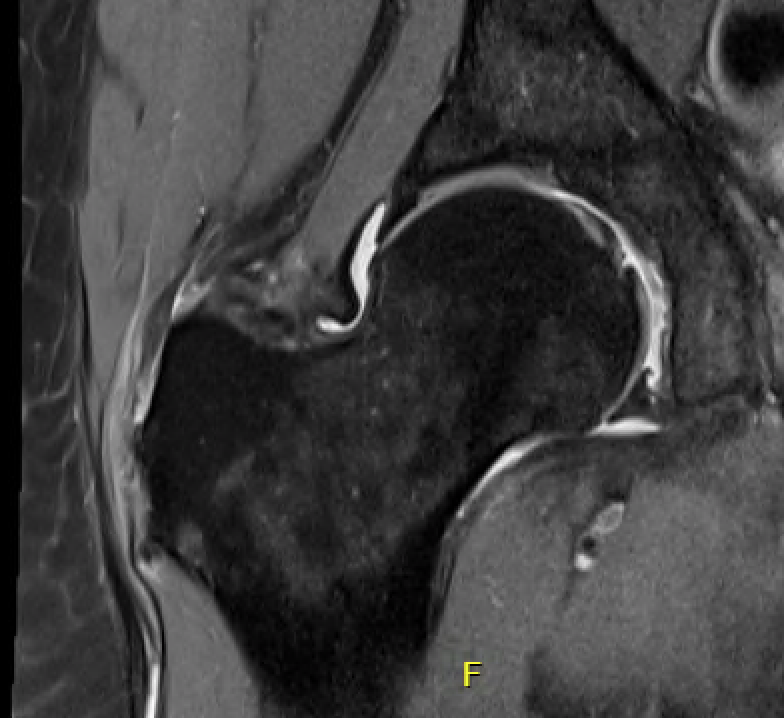

MRI

Intact gluteus medius insertion